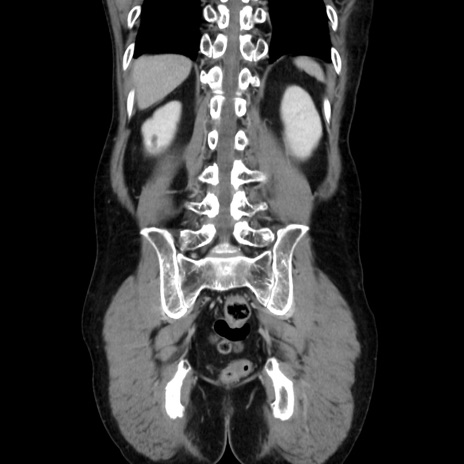

症例37(冠状断像)

【症例】40歳代 男性

【主訴】腹痛

【現病歴】4時間ほど前に電車に乗車中に臍部上より腹痛出現。徐々に増悪し起立困難となり、救急外来受診。生ものは数日食べていない。今朝お雑煮を食べた。

【身体所見】BT 36.8℃、BP 117/84mmHg、HR 91/min、SpO2 97%、苦悶様、腹部:臍上部広範囲圧痛あり、反跳痛±

【データ】WBC 8100、CRP 0.03